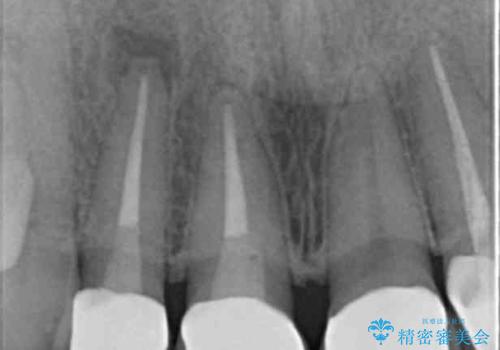

- 前歯を天然の歯のようにきれいにやりかえたいと希望され来院されました。

根尖病変の存在が判明したため、感染根管治療後にオールセラミックジルコニアクラウンを製作します。

- 37万円(仮歯×3・ファイバーコア×2・ジルコニアクラウン×3)費用は治療当時の料金となります